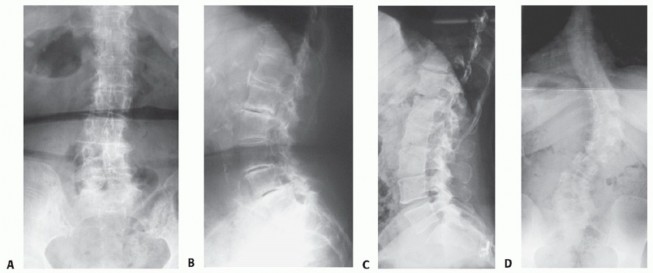

DEFINITION Adult scoliosis is a coronal deformity of the spine, typically also involving axial and sagittal p…